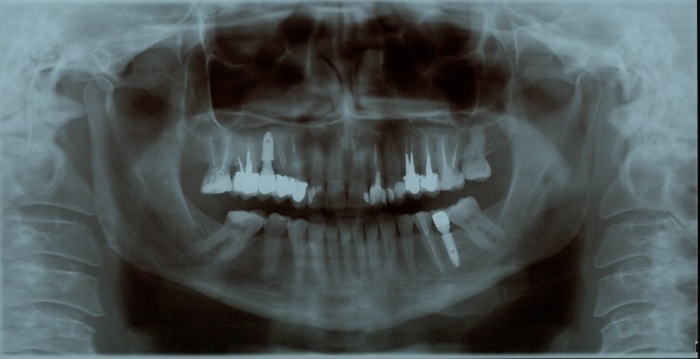

Rx Panoramico Inicial 24-07-15 - Clínica Cliniface

Rx Panoramico Inicial 24-07-15